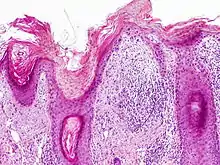

Histopathology

On histologic examination, actinic keratoses usually show a collection of atypical keratinocytes with hyperpigmented or pleomorphic nuclei, extending to the basal layer of the epidermis. A "flag sign" is often described, referring to alternating areas of orthokeratosis and parakeratosis. Epidermal thickening and surrounding areas of sun-damaged skin are often seen.[40] The normal ordered maturation of the keratinocytes is disordered to varying degrees: there may be widening of the intracellular spaces, cytologic atypia such as abnormally large nuclei, and a mild chronic inflammatory infiltrate.[41]

Specific findings depend on the variant and particular lesion characteristics. The seven major histopathologic variants are all characterized by atypical keratinocytic proliferation beginning in the basal layer and confined to the epidermis; they include:[40]

- Hypertrophic: Notable for marked hyperkeratosis, often with evident parakeratosis.[40] Keratinocytes in the stratum malphigii may show a loss of polarity, pleomorphism, and anaplasia.[22] Some irregular downward proliferation into the uppermost dermis may be observed, but does not represent frank invasion.[22]

- Atrophic: With slight hyperkeratosis and overall atrophic changes to the epidermis; the basal layer shows cells with large, hyperchromatic nuclei in close proximity to each other. These cells have been observed to proliferate into the dermis as buds and duct-like structures.[22]

- Lichenoid: Demonstrate a band-like lymphocytic infiltrate in the papillary dermis, directly beneath the dermal-epidermal junction.[40]

- Achantholytic: Intercellular clefts or lacunae in the lowermost epidermal layer that result from anaplastic changes; these produce dyskeratotic cells with disrupted intercellular bridges.

- Bowenoid: This term is controversial and usually refers to full-thickness atypia, microscopically indistinguishable from Bowen's Disease.[22] However most dermatologists and pathologists will use it in reference to tissue samples that are notable for small foci of atypia that involve the full thickness of the epidermis, in the background of a lesion that is otherwise consistent with an AK.[40]

- Epidermolytic: With granular degeneration.[22]

- Pigmented: Show pigmentation in the basal layer of the epidermis, similar to a solar lentigo.[40]